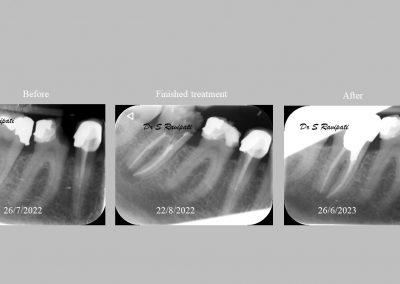

During the consultation, the dentist will first listen to your concerns and carry out appropriate tests to identify the right tooth that is causing pain. As a part of the diagnosis, your dentist will carry out various clinical tests to identify the right tooth and will take some radiographs which can aid in the diagnosis.

Files of different sizes are used to eliminate bacteria and infection and to shape the canals. The canals are disinfected thoroughly with irrigants and later the canals will be sealed in 3 dimensions with a special medicament called gutta-percha to prevent reinfection of the tooth and the access cavity will be sealed with a temporary filling.

After a few weeks, the tooth will be checked and when all the infection has cleared, a crown will be usually required to protect the restore the tooth to function.

Studies have shown thorough cleaning with instruments, disinfection and sealing the canals contribute to the successful healing of the infection and this success is reported as 95%.